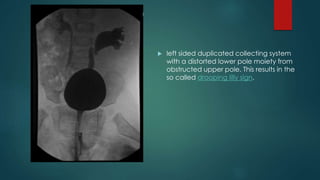

 Drooping lily sign - a urographic

sign of duplicated renal

collecting system. It refers to the

inferolateral displacement of

the opacified lower pole moiety

due to an obstructed (and

relatively unopacified) upper

pole moiety.

 In duplicated collecting system

it is classically the upper pole

ureter that is obstructed due to

a ureterocoele and the lower

pole ureter that refluxes: as

described by the Weigert-Meyer

law.

 left sided duplicated collecting system

with a distorted lower pole moiety from

obstructed upper pole. This results in the

so called drooping lilly sign.